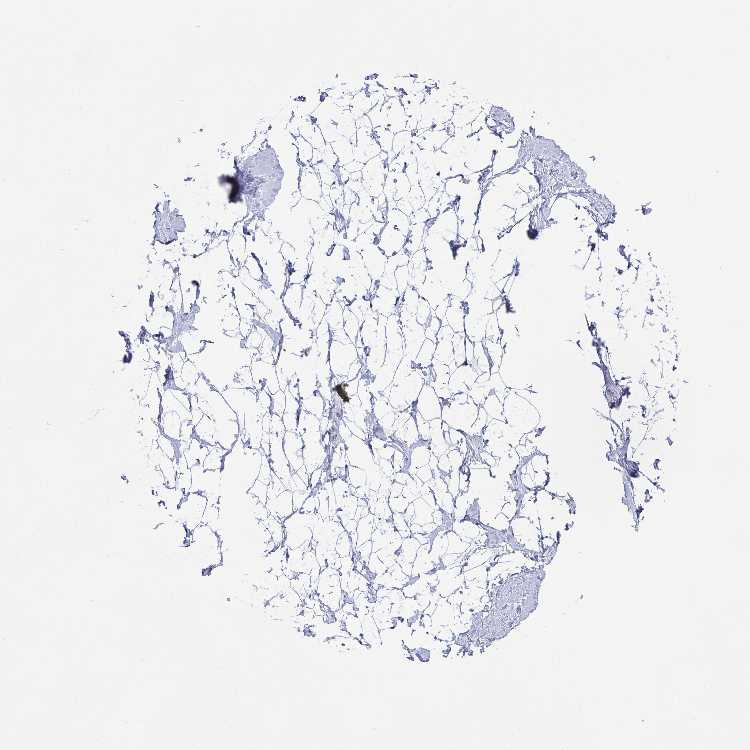

BREAST - Antibody stainingi

Antibody staining in the annotated cell types in the current human tissue is reported as not detected, low, medium, or high, based on conventional immunohistochemistry profiling in selected tissues. This score is based on the combination of the staining intensity and fraction of stained cells.

Each image is clickable and will lead to virtual microscopy that enables deeper exploration of all samples and also displays staining intensity scores, fraction scores and subcellular localization as well as patient and tissue information for each sample.

Antibody HPA059921

Adipocytes Not detected

Glandular cells Not detected

Myoepithelial cells Not detected